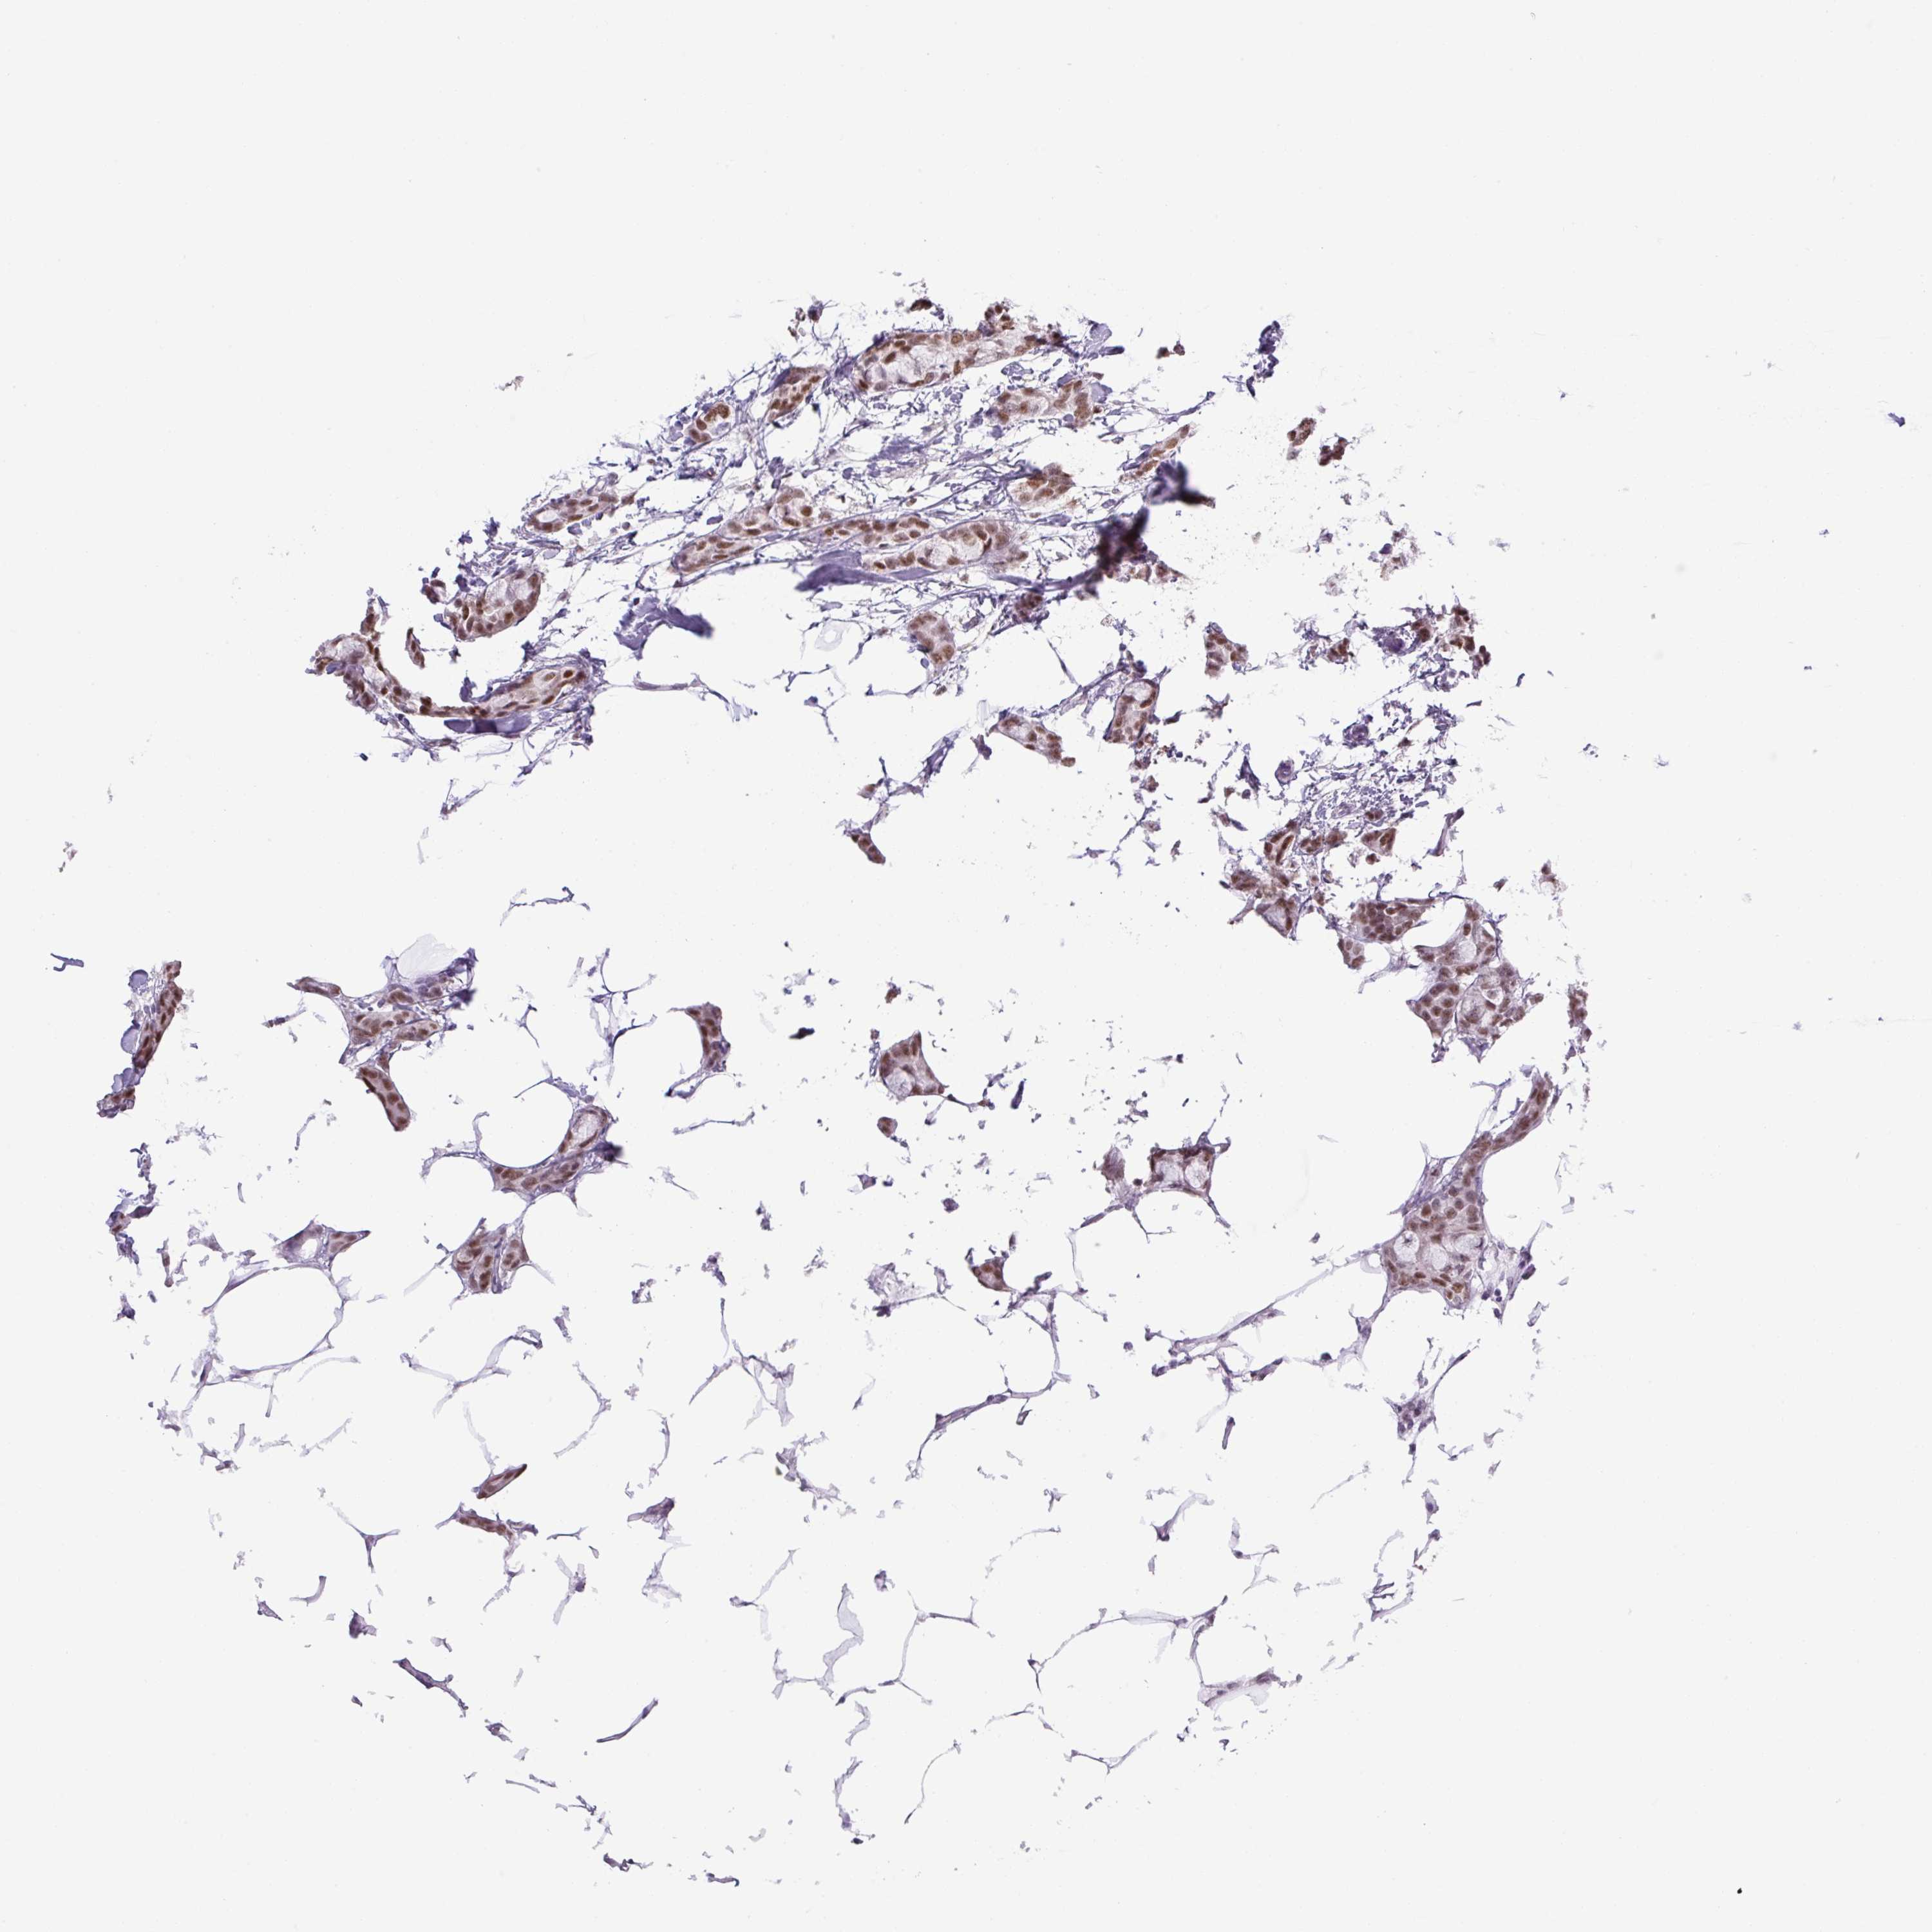

CANCER BREAST CANCER Show tissue menu

BRCA TCGA BRCA VALIDATION PROTEIN EXPRESSION

ANTIBODIES

AND

VALIDATION

Breast cancer

Human cancer